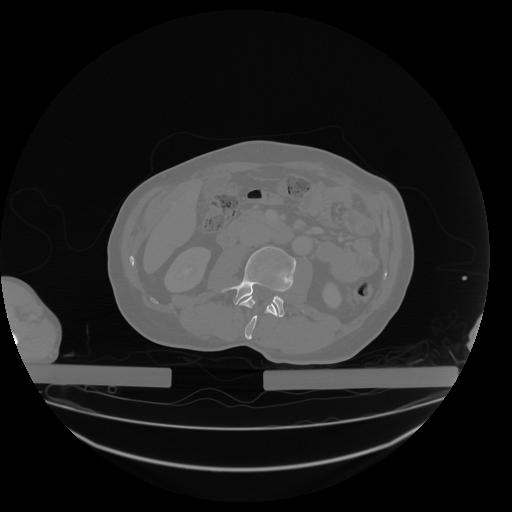

34 CUERPO,CE,Vol,1.0,CUERPO,,